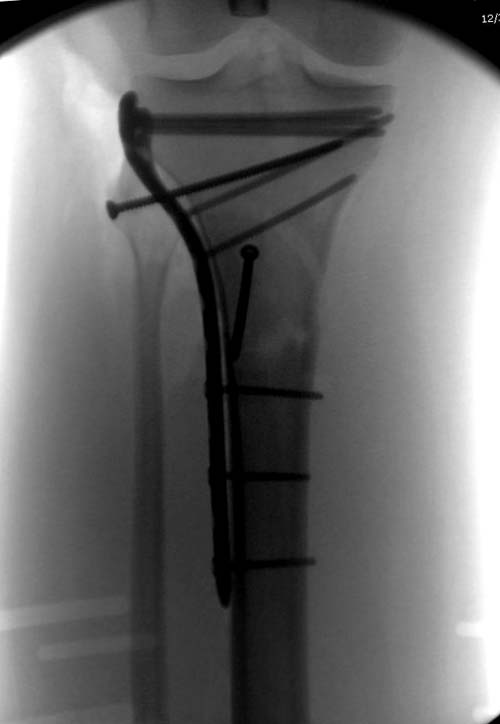

Здесь, кроме перелома верхней трети голени, имеется вовлечение сустава, и, чтобы не пропустить смещение суставной поверхности, надо делать КТ. Срезы КТ покажут о необходимости субхондральной фиксации, которая проводится 3.5 мм параллельными шурупами (Raft technique). Не имеет значения, как проводить: отдельно субхондрально или через верхний ряд пластины. Главная задача фиксации удержать суставную поверхность от коллапса в вальгус или варус.

здравствуйте! создается впечатление о фиксации перелома голени в варусном положении

Согласен, на снимке “создается впечатление о фиксации перелома голени в варусном положении”, но на других отсутствует..